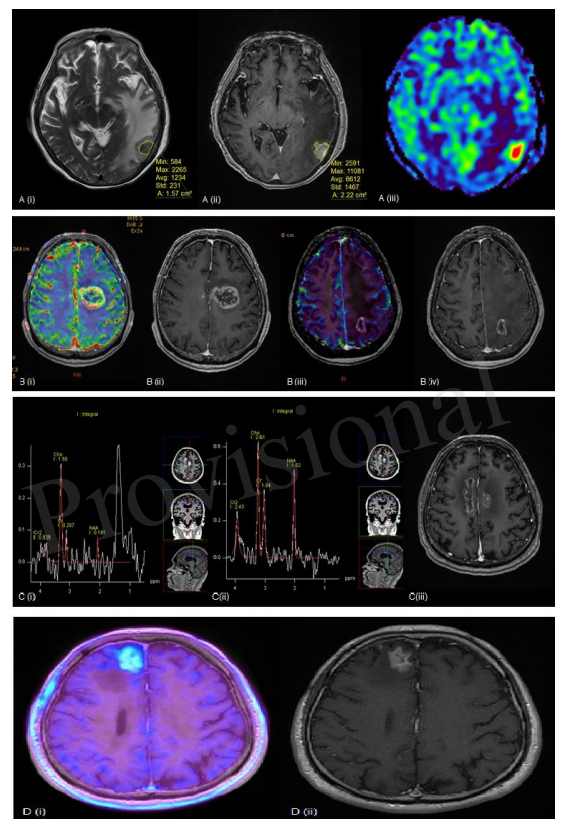

图1展示了几个例子,在这些例子中,上面的方法被用来评估放射性坏死。目前,还没有一种单一的方法可以准确区分肿瘤复发与放射性脑坏死,活检仍被认为是诊断的黄金标准。鉴于每种诊断方法的局限性,可能需要采用多种诊断方法来提高诊断信心。

图1所示。(A)(i)左侧颞叶病变的T2加权(T2W);(ii)对比增强后T1加权(T1W);(iii)相对脑血容量(rCBV)MR灌注序列。利用T2W成像上的低信号结节与T1W成像上的总增强面积之比)计算病灶商数。本病例病灶商数为0.71,rCBV增高提示肿瘤复发。(B)(i)rCBV和(ii)对比增强后T1加权序列显示病灶周围血流量增加。组织病理学证实为肿瘤复发。(iii)rCBV和(iv)另一患者对比增强后T1W序列显示,与放射性脑坏死相一致,病灶周围血流量未增加。(C)(i,ii)MR波谱分析和(iii)全脑放疗后胼胝体周围生长的病变的T1加权序列。(i)右侧扣带回的放射性坏死中典型的高脂质-乳酸峰值,而(ii)显示Cho:Cr比值和Cho:NAA比值升高,提示左侧扣带回肿瘤复发。(D)(i)F-18 FET PET显示在增强的病灶内有强烈的氨基酸示踪剂摄取;(ii)对比增强后T1加权序列,提示肿瘤复发,组织学上发现为复发性肾细胞癌转移。